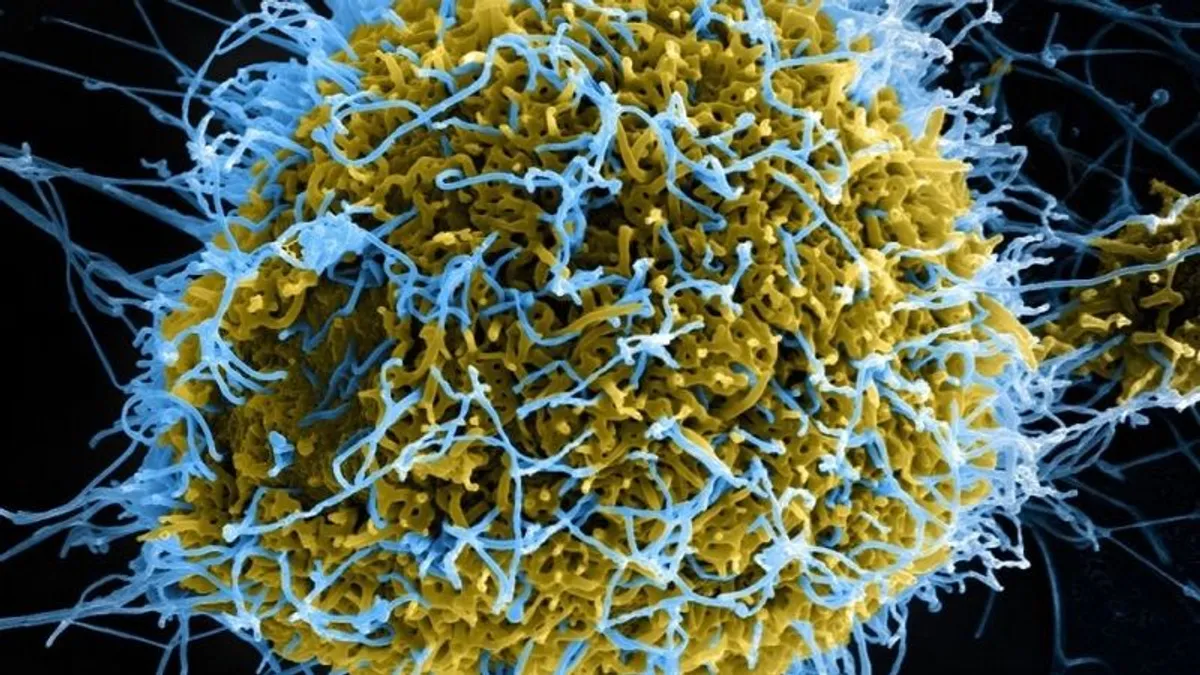

Halálos és mutálódott majomhimlő terjed nagy sebességgel, nemzetközi közegészségügyi vészhelyzetet hirdethet a WHO

A közép-afrikai országok egyre nagyobb erőfeszítéseket tesznek, hogy megállítsák a mutálódott mpox-törzs (majomhimlő) terjedését, amely január óta csak a Kongói Demokratikus Köztársaságban (KDK) közel 500 ember életét követelte. A vírus gyorsan terjed, és 2024-ben több mint 12 300 embert fertőzött meg Kongóban. A WHO most azon gondolkodik, nemzetközi közegészségügyi vészhelyzetet hirdessen-e - írta meg a Bloomberg .